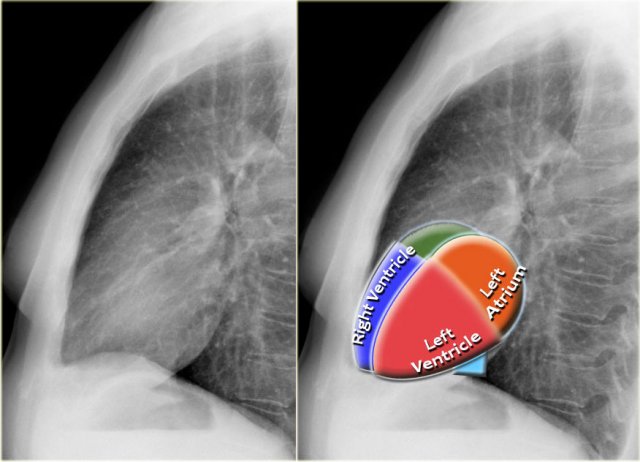

Lateral view

On a lateral chest radiograph, the cardiac borders should be well defined, and the inferior vena cava (IVC) can typically be seen entering the right atrium.

Retrosternal Clear Space

The retrosternal space normally contains aerated lung and should therefore appear radiolucent (dark on the radiograph), extending inferiorly to the level where the right ventricle contacts the sternum (small black arrow).

Any radiopacity within the upper retrosternal space is suspicious for a lesion in the anterior mediastinum or a mass arising from the upper lobes of the lungs.

Spine Sign

When evaluating the vertebral bodies on the lateral view, they should appear progressively more radiolucent (darker) from top to bottom due to the increasing amount of aerated lung overlying them (white arrow).

If the lower thoracic vertebrae appear abnormally dense, it may indicate pathology in the lower lobes, such as consolidation or mass lesions — this is known as the spine sign.

Diaphragm Evaluation

• The right hemidiaphragm should be clearly visible anteriorly up to the chest wall (red arrow), representing the interface between aerated lung and abdominal soft tissues.

• The left hemidiaphragm is usually visible only up to the point where it is adjacent to the cardiac silhouette (blue arrow), beyond which the interface is lost due to the similar radiodensity of the heart and upper abdominal contents.

Pulmonary Vasculature and Hilar Structures

The left pulmonary artery (shown in purple) arches above the left main bronchus and is situated higher than the right pulmonary artery (in blue), which courses anterior to the right main bronchus.

Understanding normal hilar anatomy on the lateral view facilitates detection of abnormalities.

Chamber-Specific Contours on Lateral View

• Left Atrium: Forms the upper posterior heart border; enlargement causes posterior bulging.

• Left Ventricle: Forms the lower posterior heart border; enlargement causes posteroinferior displacement.

• Right Ventricle: Occupies the lower retrosternal space; enlargement fills the retrosternal clear space superiorly.